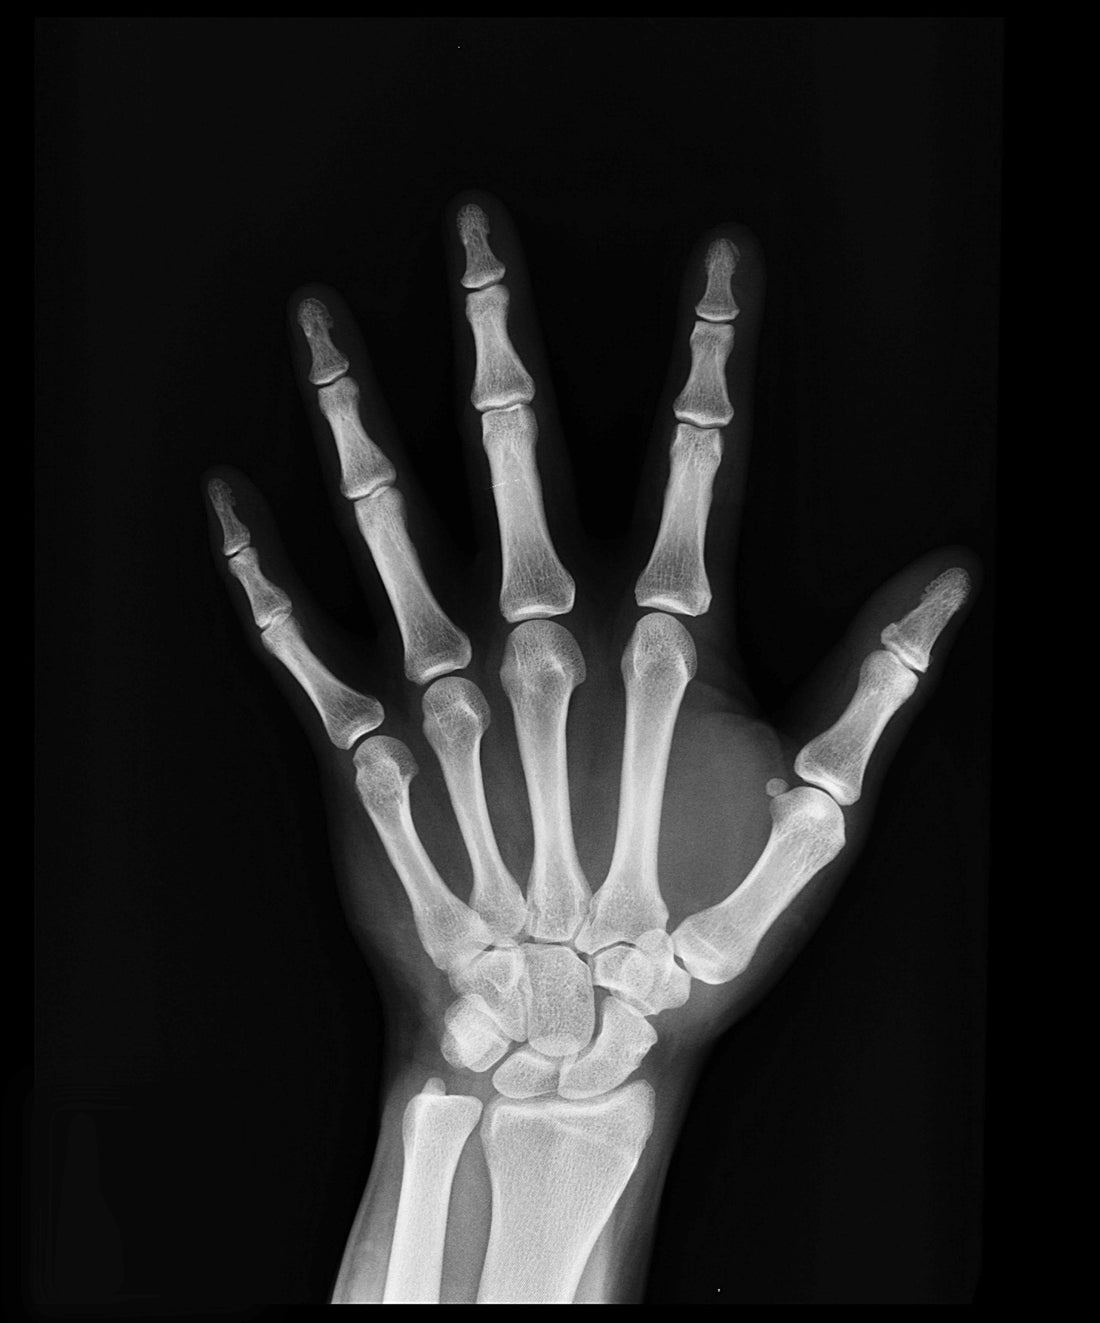

First and foremost, magnesium is a key player in bone structure. Nearly 60% of the body's magnesium is stored in the bones, where it contributes to the structural integrity of bone tissue. Magnesium works hand in hand with calcium, helping to regulate its transport and utilization within bones. In fact, magnesium stimulates the hormone calcitonin, which helps to preserve bone structure by drawing calcium out of the blood and soft tissues back into the bones where it belongs. Without adequate magnesium levels, calcium can accumulate in soft tissues, leading to calcification and potentially compromising bone health.

Furthermore, magnesium influences the activity of osteoblasts, the cells responsible for bone formation. Studies have shown that magnesium deficiency can impair osteoblast function, resulting in decreased bone formation and ultimately, weaker bones. Conversely, ensuring sufficient magnesium intake can support optimal osteoblast activity, promoting bone growth and density.

Beyond its direct effects on bone structure and formation, magnesium also plays a role in regulating bone metabolism. It helps to modulate the activity of osteoclasts, the cells responsible for breaking down old bone tissue. By maintaining a delicate balance between osteoblasts and osteoclasts, magnesium contributes to the ongoing process of bone remodeling, which is essential for maintaining bone strength and density throughout life.